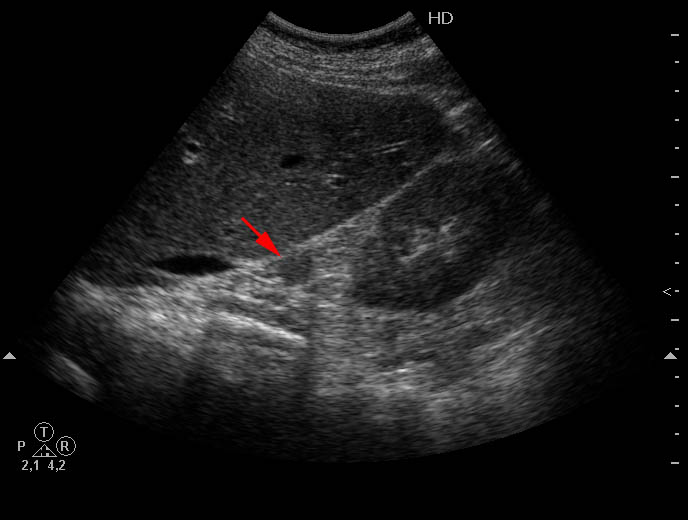

Узловая гиперплазия правого надпочечника. Right adrenal nodular hyperplasia.

Женщина средних лет, жалоб нет.